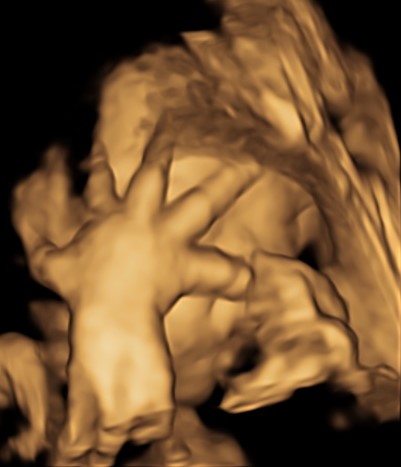

Il tesoro in ecografia è sempre più bello, infatti è da questo mese, ma soprattutto dal prossimo che comincerà ad ingrassare e diventare più tondetto per la gioia degli occhi di babbo e mamma!